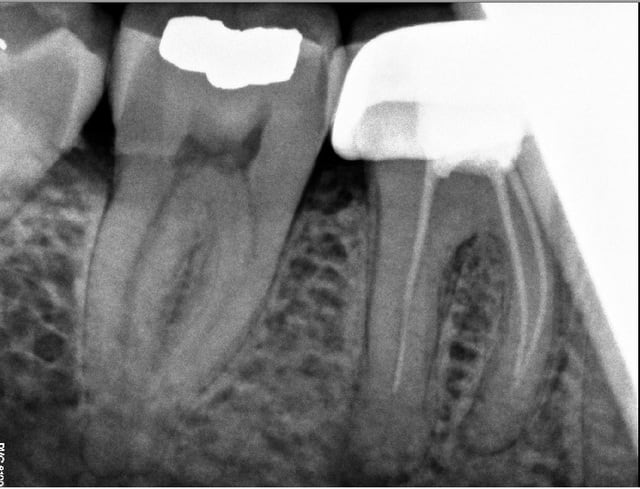

Dans le publique ils fidélisent aussi ne t'en fais pas! tiens radio classique de ce que je vois venant de la NHS... (ça a un an)